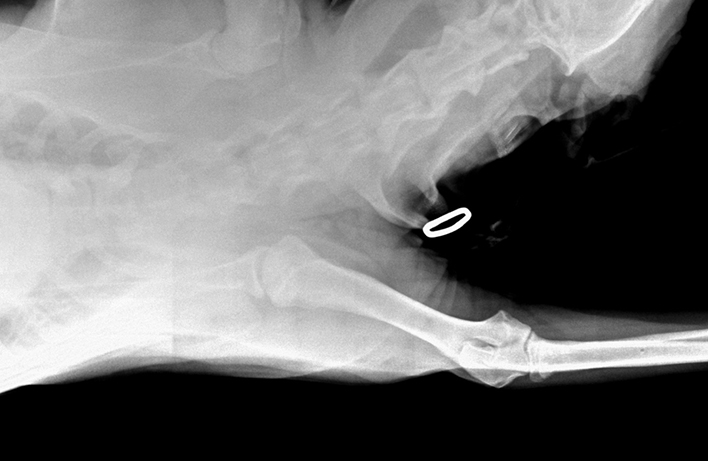

RTG Dysplazie kyčelního kloubu (DKK)